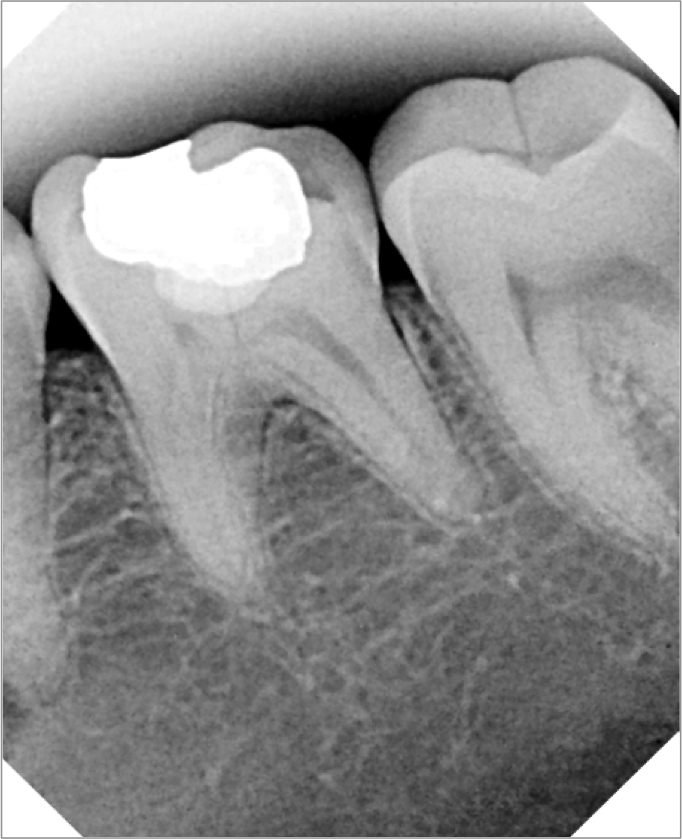

A system that prevents x-ray backscatter emits less radiation. Further, consistently good images due to receptive and efficient backing that captures x-rays across a dynamic range of settings and images that can be enlarged and enhanced without using pixilation enable doctors to capture excellent images to view and show (Figure 2 and Figure 3).

Figure 2 and Figure 3. The enhancement tools available with many digital imaging systems can help bring to light anatomic detail to increase diagnostic accuracy and case acceptance.